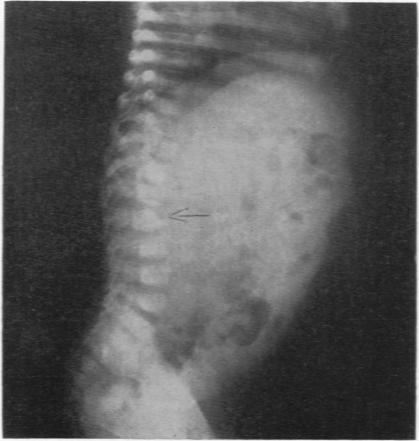

BABER M D

Arch Dis Child. 1956 Oct;31(159):335-9. doi: 10.1136/adc.31.159.335.